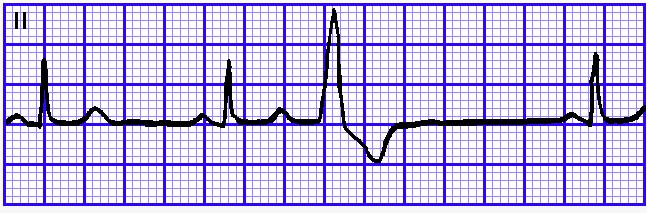

2、宽大畸形

QRS波群的宽大畸形主要是指该波群时间超过0.12s,临床上常见于室性心律,其次是室性逸搏、室内差异传导,举例聊聊三者:

室性早搏:室性早搏关键在一个“早”字,提前激动的,宽大畸形的QRS波群就是室性早搏,因为提前激动,所以叫早搏,要记住“早”这个字,室性早搏也就理解个百分之八九十了,剩下的在去区分单源性或多源性,单发、偶发还是频发,以及严重的R-on-T现象。

图4